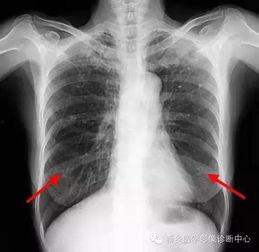

首先,得先弄清楚什么是胸片。胸片,顾名思义,就是通过X射线对人体胸部进行拍摄的一种医学影像检查。它能够清晰地显示出心脏、肺部、纵隔等器官的结构和形态,对于诊断各种胸部疾病有着至关重要的作用。

1. 肺部疾病诊断

胸片检查是诊断肺部疾病的重要手段。通过观察肺部影像,医生可以初步判断患者是否患有肺炎、肺结核、肺癌等疾病。